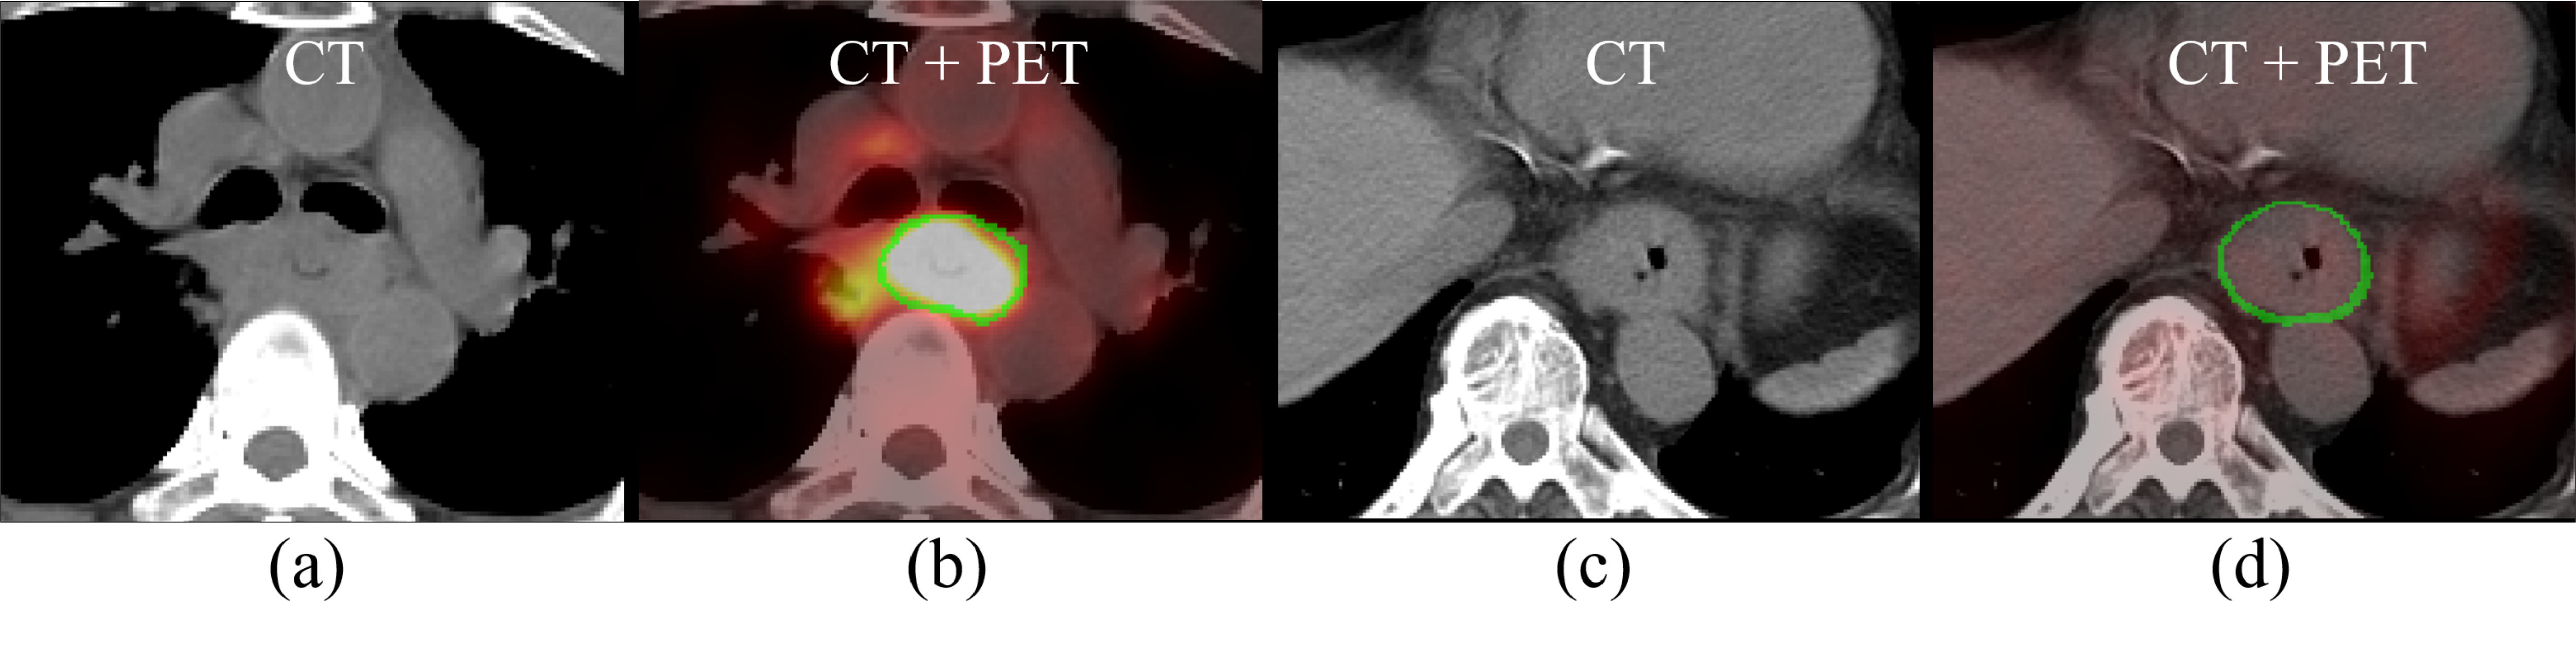

Deep \acpCNN have made remarkable progress in the field of medical image segmentation [2, 3, 8, 9, 4]. Yet, only a handful of studies have addressed automated esophageal \acGTV segmentation [16, 15], all of which rely on only the \acRTCT images. The assessment of \acGTV by \acsCT has been shown to be error prone, due to the low contrast between the \acGTV and surrounding tissues [12]. Within the clinic these shortfalls are often addressed by correlating with the patient’s \acPET/CT scan, when available. These \acpPET/CT are taken on an earlier occasion to help stage the cancer and decide treatment protocols. Despite misalignments between the \acPET/CT and \acRTCT, \acsPET still provide highly useful information to help manually delineate the \acGTV on the \acRTCT, due to its high contrast highlighting of malignant regions [11]. As shown in Fig. 1, \acCT and \acsPET can each be crucial for accurate \acGTV delineation, due to their complementary strengths and weaknesses. While recent work has explored co-segmentation of tumors using PET and CT [18, 17], these works only consider the \acPET/CT image. In contrast, leveraging the diagnostic \acPET to help perform \acGTV segmentation on an \acRTCT image requires contending with the unavoidable misalignments between the two scans acquired at different times.

Refer to caption

Figure 1: Esophageal GTV examples in CT and PET images, where the green line indicates the \acsGTV boundary. (a)-(b): although the GTV boundaries are hardly distinguishable in CT, it can be reasonably inferred with the help of the PET image, in spite of other false positive high-uptake regions. (c)-(d) here, no high uptake regions appear in PET; however, the esophagus wall enlargement evident in CT may indicate the GTV boundary [6].